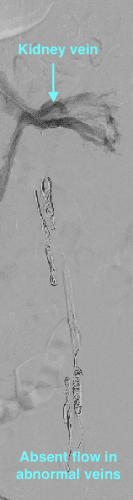

Varicocele can be treated by an embolization procedure or surgery. Embolization is a non-surgical, outpatient, minimally invasive technique that uses x-ray guidance to place tiny coils and embolic fluid in the abnormal blood vessels causing them to close down.

After a local anesthetic, a tiny catheter is placed into a vein in the groin or neck. The Interventional Radiologist then uses the x-ray equipment to guide the catheter into the variococele. A combination of metallic coils and a special fluid are placed directly into the abnormal veins causing them to close. Once the veins are blocked, the catheter is removed.